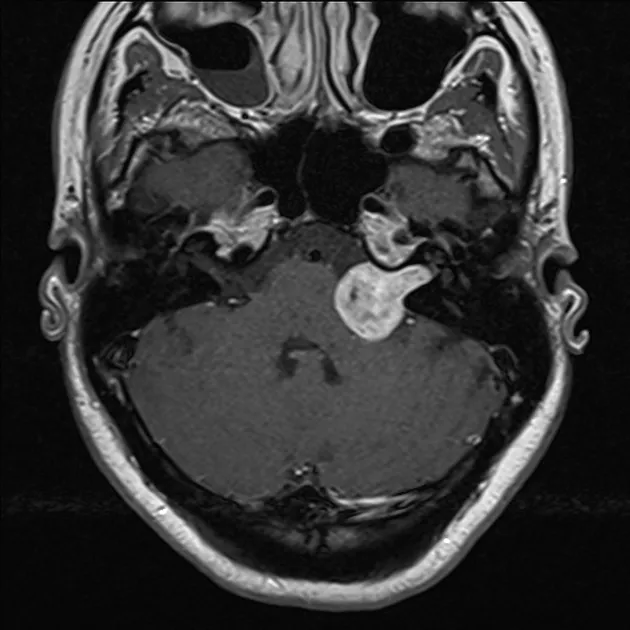

- MRI with Gadolinium: Gold Standard.

⭐ MRI with gadolinium contrast is the gold standard for diagnosing acoustic neuroma, often showing an "ice cream cone" appearance.